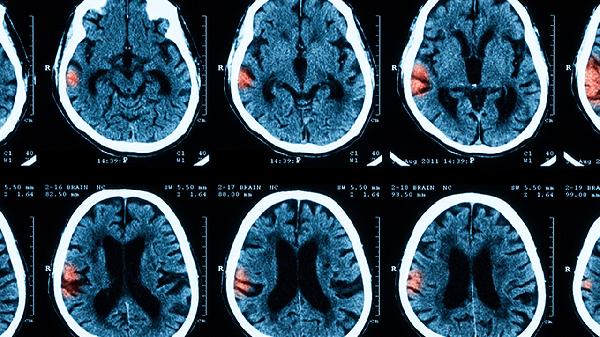

细菌性脑膜炎是最严重的类型,常见病原体包括脑膜炎奈瑟菌、肺炎链球菌和流感嗜血杆菌。这类感染进展迅速,患者可能出现高热、剧烈头痛、颈项强直等症状,若不及时治疗可导致脓毒血症、脑水肿甚至死亡。治疗需静脉注射抗生素如头孢曲松、万古霉素等,并密切监测颅内压。

隐球菌性脑膜炎多见于艾滋病患者,起病隐匿但危害严重。临床表现为慢性头痛、低热和认知障碍,易误诊为偏头痛。未及时治疗可导致脑积水、视力丧失,死亡率达40%。需长期使用两性霉素B联合氟胞嘧啶治疗。

严重并发症显著增加疾病风险,包括脑疝、癫痫持续状态和多器官衰竭。约20%幸存者遗留听力丧失、运动障碍等后遗症。急性期需通过脱水降颅压、抗惊厥等综合治疗降低致残率。